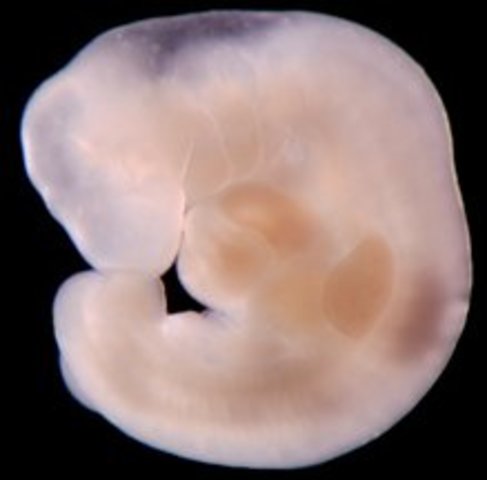

• Week Five

Week Five

The embryo is now the size of a pin head and by the end of the week it wil have more than doubled in size. The placenta is developing and the embryo starts reveiving oxygen and nutrients.

• Week Six

Week Six

All major organs and systems are forming, including the heart. The heart will begin to beat on the 25th day of conception.